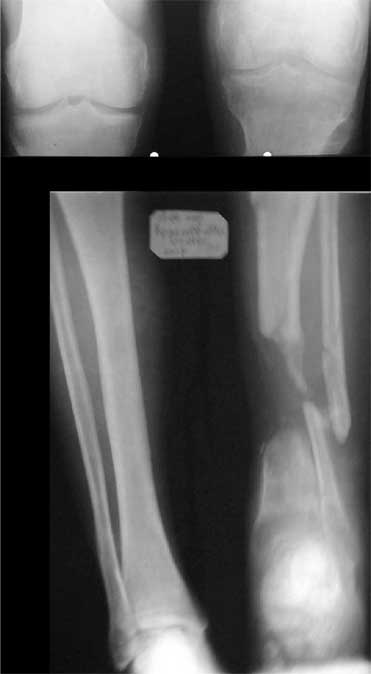

В приложении - моё наблюдение (возможно, уже представлял, тогда

извините).

Нога попала в пресс.

Ко мне больной попал черз 1,5-2 года после травмы и нескольких

операций с синегнойной инфекцией на всю голень. Меня пригласили на консультацию

насчет ампутации.

Лечил я его месяцев 8.

Малоберцовка полностью перестроилась, нога опороспособна.

При ходьбе на дальние расстояния пользуется тростью.

Осталась трофическая язва, периодически закрывается.

Клинические снимки где-то есть, но не очень качественные.

Один из вариантов.

С уважением Александр Артемьев

К сожалению на первичной и последующей рентгенограммах не видно, что творится с голеностопным суставом. Если вилка суства сохранена, то есть смысл побороться за конечность. Интересно, увитеть, что твориться с голеностопным суставом.